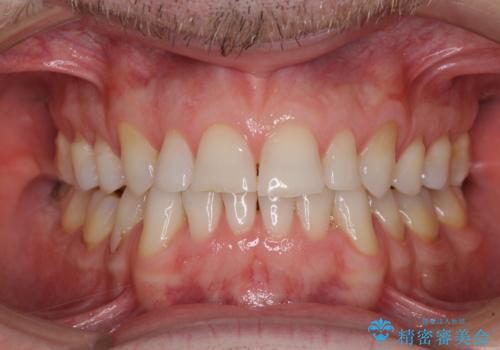

- 上下前歯の叢生を気にして来院された患者様です。

抜歯矯正をした後戻りということで、歯列不正はそれほど大きくなかったため、インビザライン・ライトを用いて矯正治療を行うこととしました。

前歯のデコボコが残っており、シミュレーション通りに動いていない部分がありましたが、再矯正であることやご本人の満足いくところまでデコボコが改善されたとのことで、治療を終了することとしました。